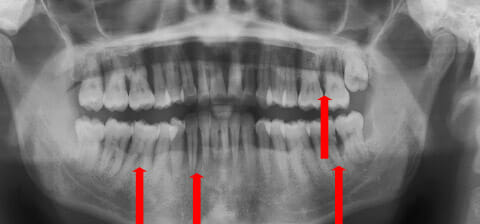

Panoramica prima e dopo la terapia parodontale con laser e microscopio

Con terapia parodontale fotodinamica non chirurgica: si noti la ricrescita naturale dell’osso e del tessuto parodontale.